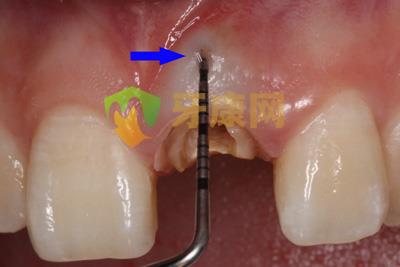

根管側穿修補術,根管側穿是牙髓治療失敗的一個重要原因,常常由不正確的開髓、根擴方法導致,樁核制作時盲目的操作也會造成側穿,側穿部位越及時修補,增加治療成功的可能性越高,下面是根管側穿修補術的一個病例:

患者外院螺紋樁核加樹脂冠,唇側出現瘺管

瘺管